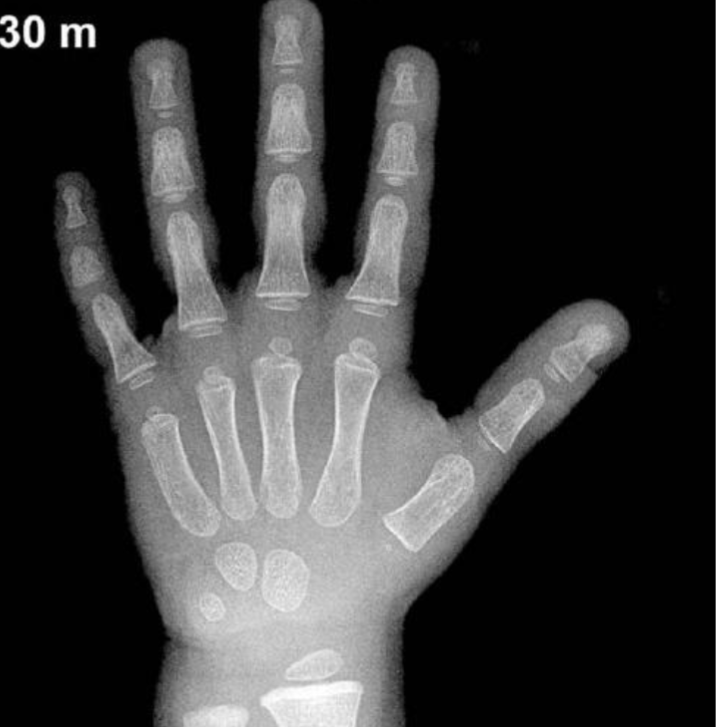

- X-ray of the left hand

- 3 abnormalities in X-ray

Child with Rickets - 18-month-old infant has bowing legs and is not growing properly. He was exclusively breastfed until 11 months of age.

- Mention 2 abnormalities sign in this pictures?

- Rachitic rosary (Knobby deformities)

- Leg bowing

- What is your diagnosis?

- Rickets

- d. Thyroid stimulating hormone (TSH). What are the findings in the X-ray images? Widened metaphysis, osteopenia, cupping, and wide, frayed appearance.